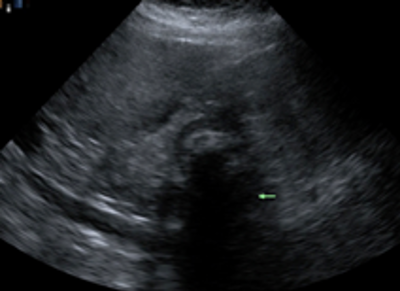

Abdominal ultrasonography (Figures 1 and 2) showed the gallbladder to be abnormal and completely filled with stones. The gallbladder wall was thickened, measuring up to 7 mm—a finding consistent with acute calculous cholecystitis. No definite fluid was seen in the gallbladder fossa, and no dilated common bile duct was noted.

Figure 1. Abdominal ultrasonography showing acoustic shadowing due to the presence of gallstones.